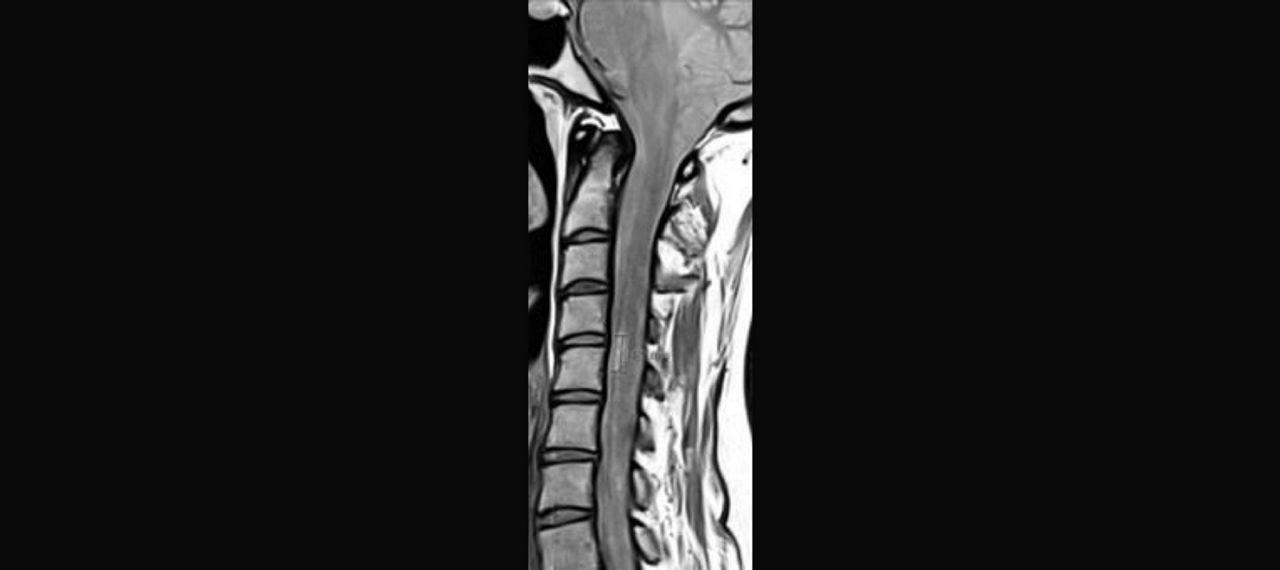

Abb. 1: Bei Vorstellung großflächige Läsion

Abb. 2: Leichte Besserung

Abb. 3: Nach 2 Monaten: Ausweitung der flächigen Läsionen mit zystischen Anteilen

- Schwere Encephalopathie

Abb. 4: Nach 2 Monaten

Abb. 5: Nach 2 Monaten; perlschnurartige kontrastmittelaufnehmende Herde über das gesamte Myelon

Abb.6: 4 Monate nach Vorstellung: Zunahme der flächigen Marklage-Läsionen und der zystischen Defekte